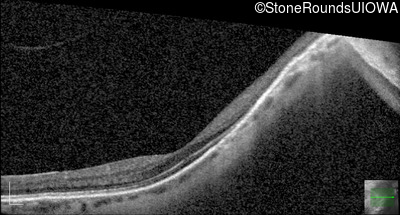

Optical Coherence Tomography - Right - 20/40 +2

Exemplar / OCT Stack